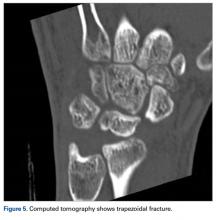

Later, however, the hand surgery team evaluated the radiograph as well as computed tomography (CT) scans and found a translunate, transradial, transtriquetral, transtrapezoid perilunate dislocation of the wrist with multiple metacarpal neck fractures ( Figures 1-5 ).The next day, with the patient under general anesthesia, an attempt to reduce the perilunate dislocation by manipulation was unsuccessful. Open reduction and internal fixation (ORIF) were performed through a dorsal approach; the perilunate dislocation was reduced and stabilized with lunocapitate 1.2-mm Kirschner wire (K-wire). The scapholunate and lunotriquetral ligaments were found to be intact, and the significantly displaced triquetral fracture was treated with internal fixation involving 2 minifragment screws ( Figure 6 ).